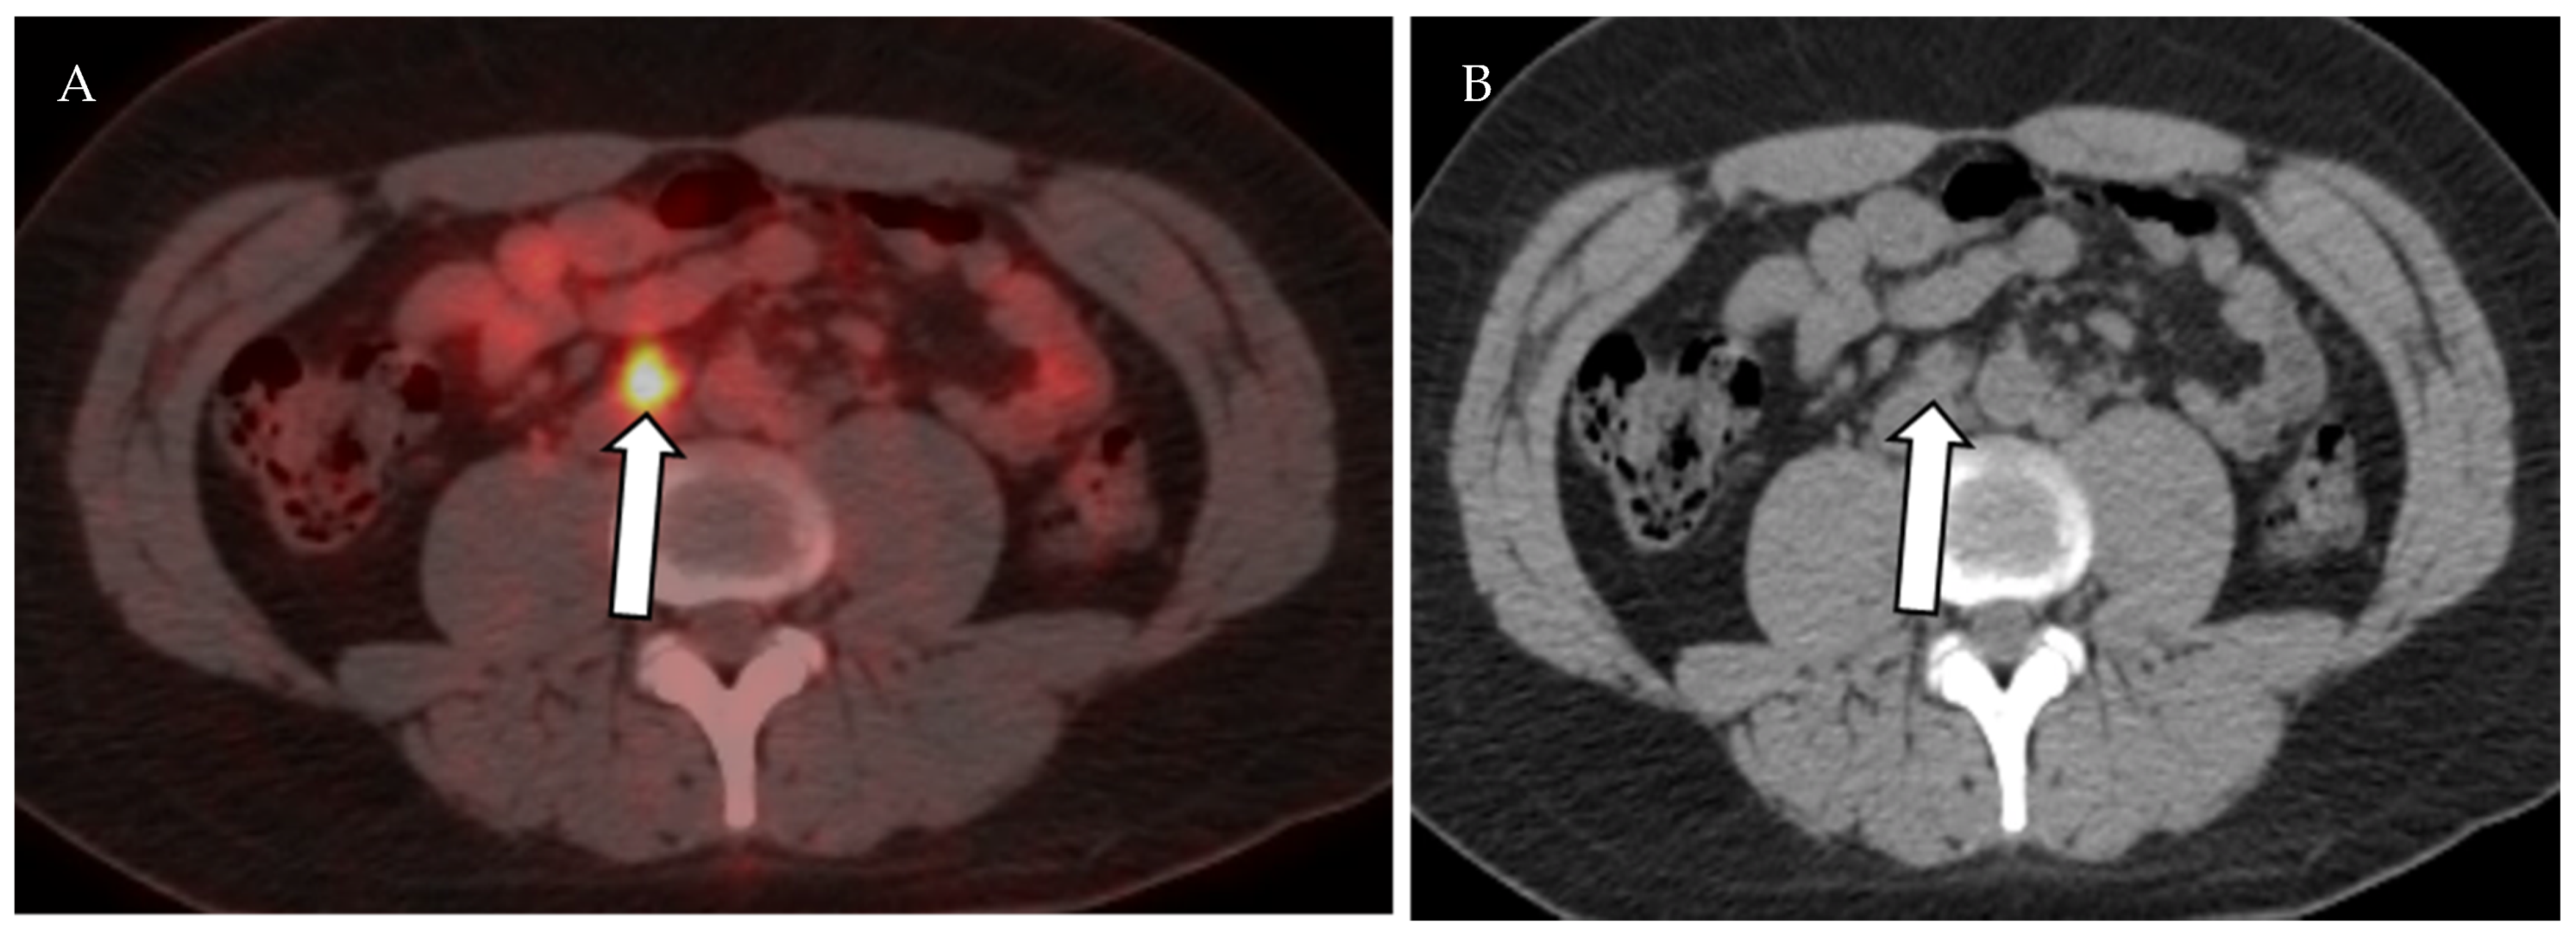

4.1.3. Positron Emission Tomography (PET) and Positron Emission Tomography-Computed Tomography (PET-CT)